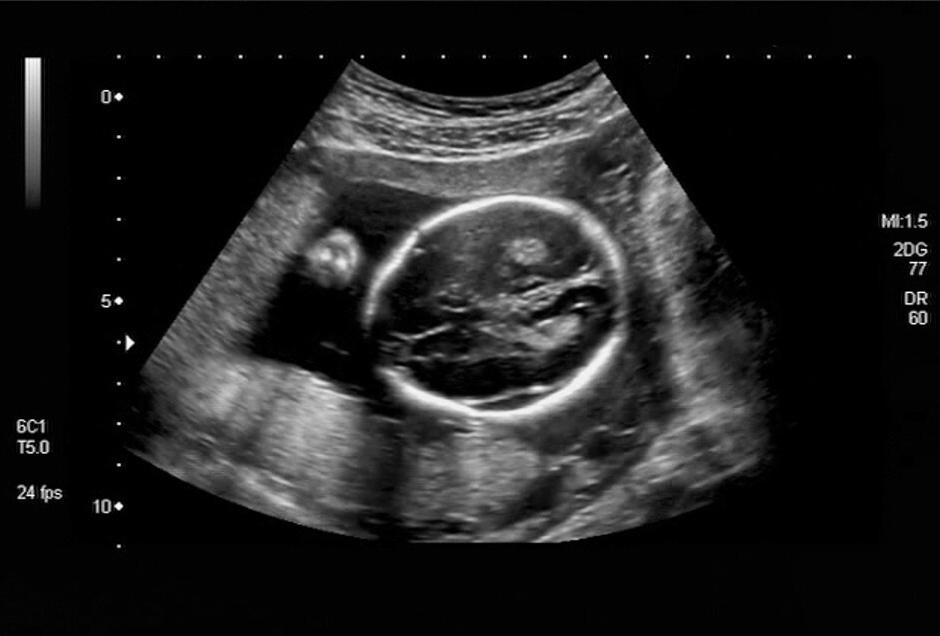

浑浑噩噩的去给医生看报告,开B超,结果B超什么都没有看到,基本确定是生化了。

但此时,超声检查还不能发现孕囊的存在。由于某些原因,胚胎不能继续发育而枯萎,随后以月经出血的形式结束,这种现象叫生化妊娠。

通常,胚胎着床后5~6周,可通过超声检查看到孕囊,此时进入临床妊娠阶段。